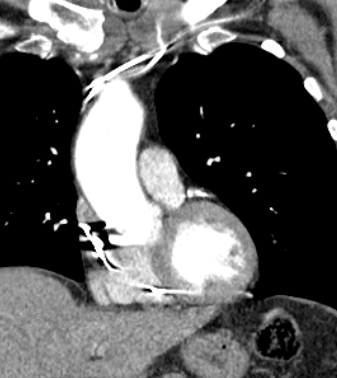

Another month later the patient presented to A&E with chest pains and a sensation that the pacemaker was delivering shocks. The CT report from the previous week was chased and revealed the following.

“Dual-chamber cardiac pacemaker is noted in situ. The tip of the right ventricular lead is seen located beyond the confines of the myocardium and abutting the pericardium. Features suggest RV lead perforation of the myocardium, on the background of clinical history provided. Urgent specialist Cardiac review is recommended.

The lead is seen traversing through the pericardial space. However, the pericardium appears grossly intact. No evidence of pericardial effusion”

Figure 4 – CT scan image showing the RV lead tip within the pericardial space